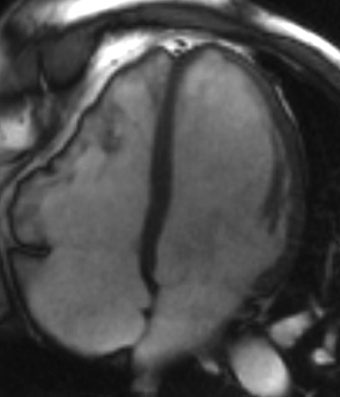

Resonancia magnética cardiaca

La resonancia magnética cardiaca es un una técnica de imagen que permite estudiar detalladamente y en una sola exploración la función y la estructura del corazón. Este auxiliar diagnóstico utiliza un potente campo magnético, sin radiación, para generar imágenes detalladas de las estructuras del corazón.

La resonancia magnética esta indicada en la evaluación de las cardiopatías congénitas tanto en el niño como en el adulto, en la evaluación de la perfusión miocárdica (resonancia cardiaca con gadolinio), de la función cardiaca, de las enfermedades del músculo cardiaco (miocardiopatías), tumores del corazón y del tejido que rodea al corazón (pericardio).

Este estudio es bien tolerado por la mayoría de las personas. El campo magnético no es dañino, pero puede causar el mal funcionamiento de algunos dispositivos médicos. La mayoría de los implantes ortopédicos no presentan riesgos, pero siempre debes informar al técnico de resonancia magnética si tiene algún dispositivo o metal en su cuerpo.